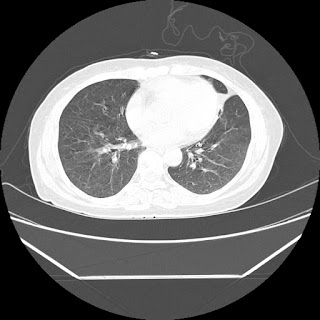

HRCT is also done on 13/11/15